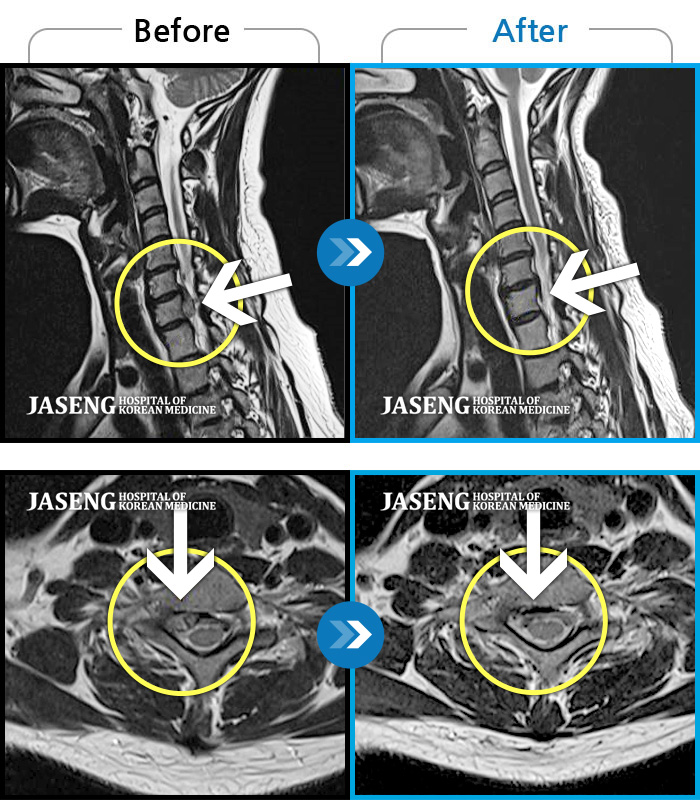

김준수 원장님께 진료 받은지가 벌써 3년이 넘은거 같습니다. 한결같이 늘 환하게 웃으시면서 환자 개개인의 증상에 맞게 설명과 치료를 해주시며 그 많은 환자들을 대하실 때 참으로 진정한 의료인이시구나 하는 생각을 하게 됩니다. 오늘도 MRI 판독 결과를 세세 하게 짚어가며 설명을 해주셨는데 눈물 나게 감사함을 느꼈습니다 제가 걱정을 하니 차분하게 위로를 해주시면서 안정을 시켜주시니 감사할 따름이었습니다 입원기간 느끼는건데 별 보며 출근하시고 별보며 퇴근 하시나?할 정도로 열과 성의를 다 하시는 모습에 모든 입원 환자들이 원장님을 좋아하는걸 보니 참 의료인이라는 생각이 듦에 칭찬합니다. 그리고 내 영원한 주치의로 모셔야 겠다..